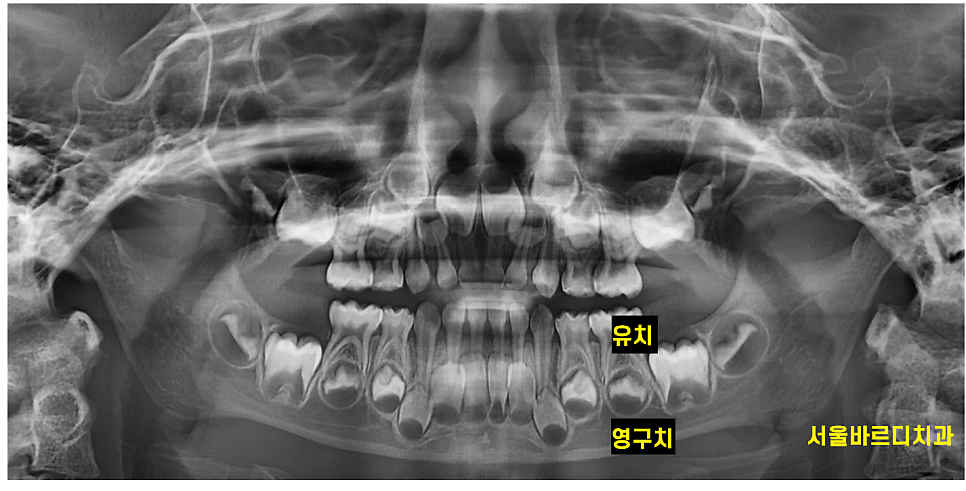

첫번째, 영구치 배열에 영향을 줍니다.

유치 뿌리가 녹으면서 영구치가 올라오는데요~

영구치가 자리를 잡을 공간을 유지하는 역할을 합니다!

때문에 충치라던가 다른 이유로 너무 빨리 빠지게 되면

주변 치아가 빈 공간으로 이동

영구치가 올바른 위치에 나오지 못할 가능성이 있어요!

(덧니가 나올 수 있다는 말이죠..)

문제는 유치 바로 밑에 영구치 씨앗이 위치한다는 것인데요.

영구치까지 염증이 퍼져 영향을 미칠 수 있다는 점이에요!

이렇게 되면 영구치가 올라와도 건강하지 않을 수 있답니다.

240724 유치 밑에 영구치가 있어요~!!